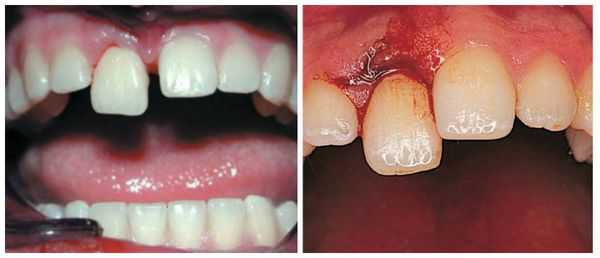

- Неполный вывих : боль усиливается при контакте с зубом, например во время приёма пищи; на слизистой оболочке полости рта имеются маленькие ранки, ссадины и гематомы; мягкие ткани отёчны; наблюдается смещение зуба в сторону и его значительная подвижность; вынужденное положение челюсти в связи с наличием болевых ощущений.

- Полный вывих: сопровождается сильной болью; зуб в лунке отсутствует; пустая лунка кровоточит; десна изменена в цвете; имеется припухлость; может возникнуть гематома; происходит локальное повышение температуры; некоторое время могут наблюдаться дефекты речи.

- Вколоченный вывих : пациент чувствует постоянную боль, усиливающуюся при давлении, жевании, смыкании челюстей; при пальпации десны появляется её гиперемия (покраснение) и отёчность; возникает незначительное кровотечение из места травмы. Что интересно, при перкуссии (постукивании) травмированного зуба человек не ощущает болевых ощущений и дискомфорта. При визуальном осмотре заметно укорочение зуба или же он полностью "спрятан" в лунке, при этом неподвижен.

Для всех видов вывиха характерна следующая симптоматика: боль в области причинного зуба, кровоточивость, отёчность десны.

Лечение неполного вывиха

Если у пациента наблюдается неполный вывих, то лечение начинают с проводникового обезболивания, после чего врач аккуратно репонирует (устанавливает в лунку) зуб. Репозиция проведена правильно, если при смыкании челюстей отсутствует соприкосновение травмированного зуба с антагонистом.

После проведённых лечебных мероприятий вывихнутый зуб иммобилизируют (обездвиживают). Для этого врач использует индивидуальную шину-каппу, изготовленную непосредственно на пациенте. В шину обязательно включают не менее двух здоровых зубов по обе стороны от неполного вывиха. Шину накладывают минимум на 5-6 недель.

Лечение полного вывиха

В случае полного вывиха зуба, если с момента травмы прошло не более двух суток, проводится его реплантация (установка зуба обратно в лунку) [8] .